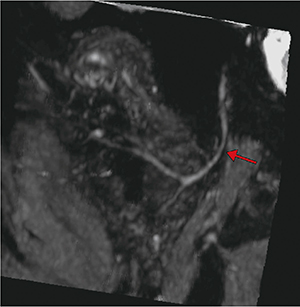

まずは,元画像のまま(図1 a),次にMPR(図1 b)で観察を行い,ほかにsliding MIP(図2 a),curved MPR(図2 b)などでの観察が考えられる。しかし,元画像のままでは,構造が細く画像の解釈が困難である。また,MPR,sliding MIPでは観察可能であるものの,断面をその都度ずらす必要があり,神経全体の観察には適していない。curved MPRでは,細部まで神経の走行を追跡できるものの,1本の神経しか描出できず,分岐していく神経には対応できない。このように,これまでの描出方法では分岐していく神経全体像をとらえることは困難であった。

図1 耳下腺内顔面神経の描出方法:元画像とMPR